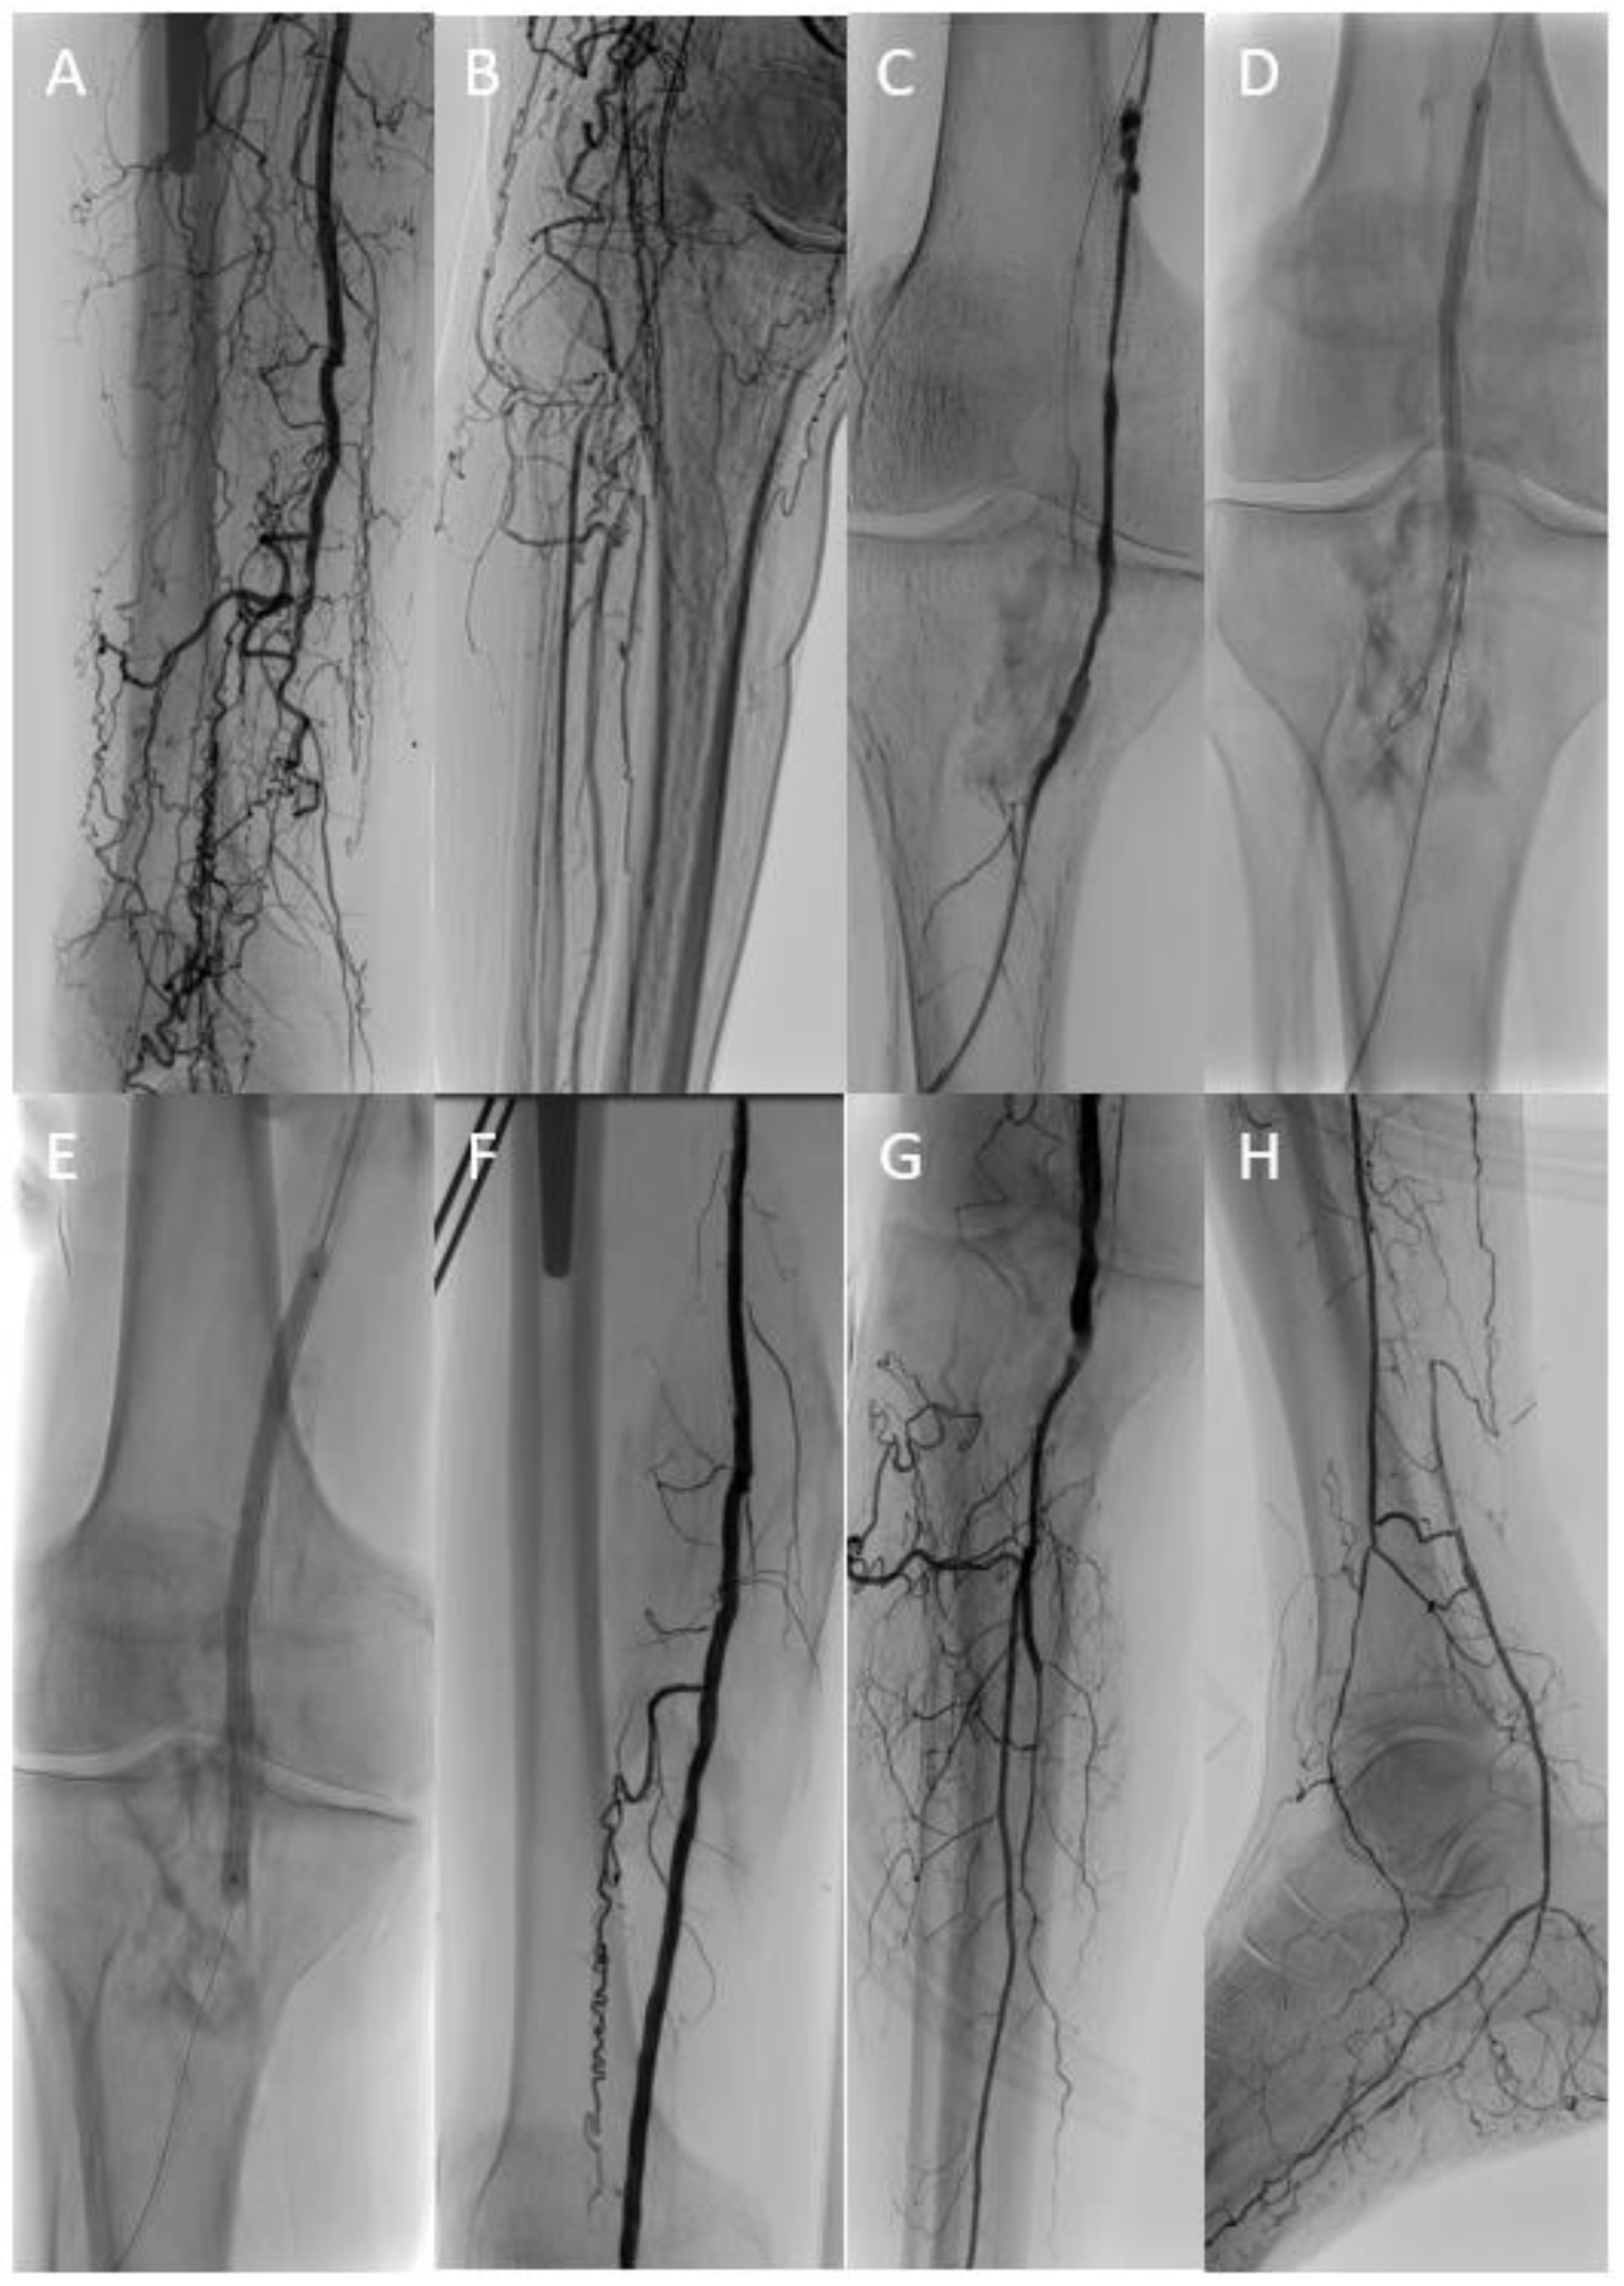

Figure 2.

In a patient with critical limb ischemia and femoropopliteal occlusion (A,B), conventional recanalization attempts of the native artery and the chronically occluded femoropopliteal vein graft (C) were unsuccessful. Finally, target balloon-assisted re-entry with a retrogradely inserted GoBack™ catheter (D) enabled successful wire passage and adjunctive therapy of the native femoropopliteal segment (E–G) with a single-vessel run-off (H).